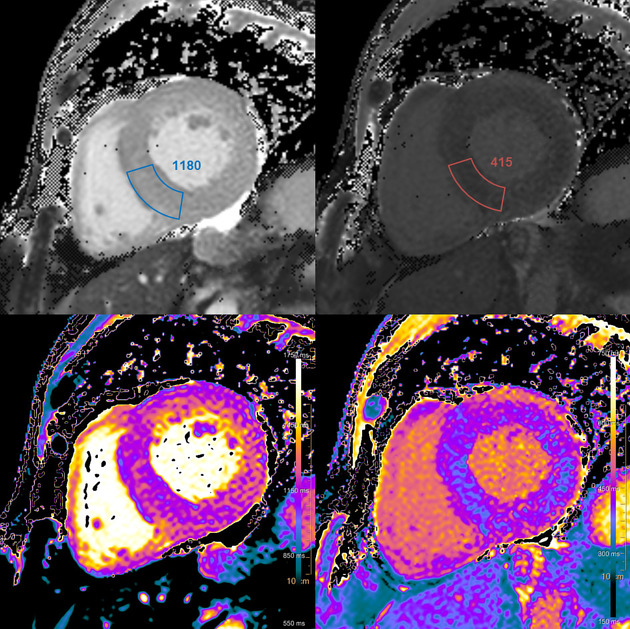

6) 심장 자기공명영상

- 심장자기공명영상 : 민감도가 높은 검사법

출처 : https://radiopaedia.org/articles/cardiac-amyloidosis

Cardiac amyloidosis | Radiology Reference Article | Radiopaedia.org

Cardiac amyloidosis (plural: amyloidoses) is a significant source of morbidity among patients with systemic amyloidosis and is the most common cause of restrictive cardiomyopathy outside the tropics. Pathology Amyloidosis represents the extrace...

radiopaedia.org